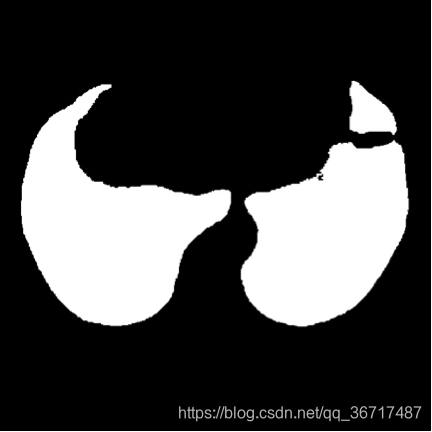

- 肺部区域提取。使用图像分割算法生成肺部区域的mask图,然后根据mask图生成肺部区域图像。

- 疑似肺结节分割。

利用肺部分割生成的肺部区域图像,加上结节标注信息生成的结节mask图像,训练基于卷积神经网络的肺结节分割器。下图基于卷积网络的肺结节分割结果,对分割结果图像进行二值化,提取连通块等处理,提取出疑似肺结节。由于CT图像是一个扫描序列,参赛者可能需要对多帧的结果进行融合。